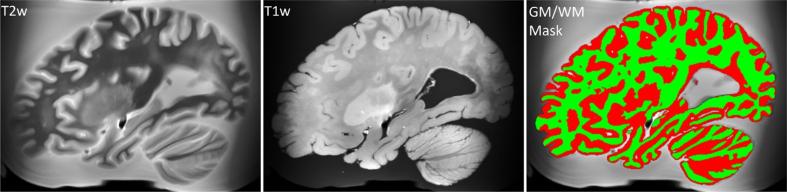

METHODS

Using four different MRI sequences, we are reaching a sample size that allows for validating multimodal neuroimaging biomarkers and studying comorbid conditions. Our imaging protocol was designed to capture markers of cerebrovascular disease and related lesions. Quantification of these lesions is currently underway with MRI-guided histopathological examination.

我们使用四种不同的 MRI 序列,样本量达到了验证多模态神经影像学生物标志物和研究合并症的要求。我们的成像方案旨在捕获脑血管疾病和相关病变的标志物。目前正在通过 MRI 引导的组织病理学检查对这些病变进行定量分析。